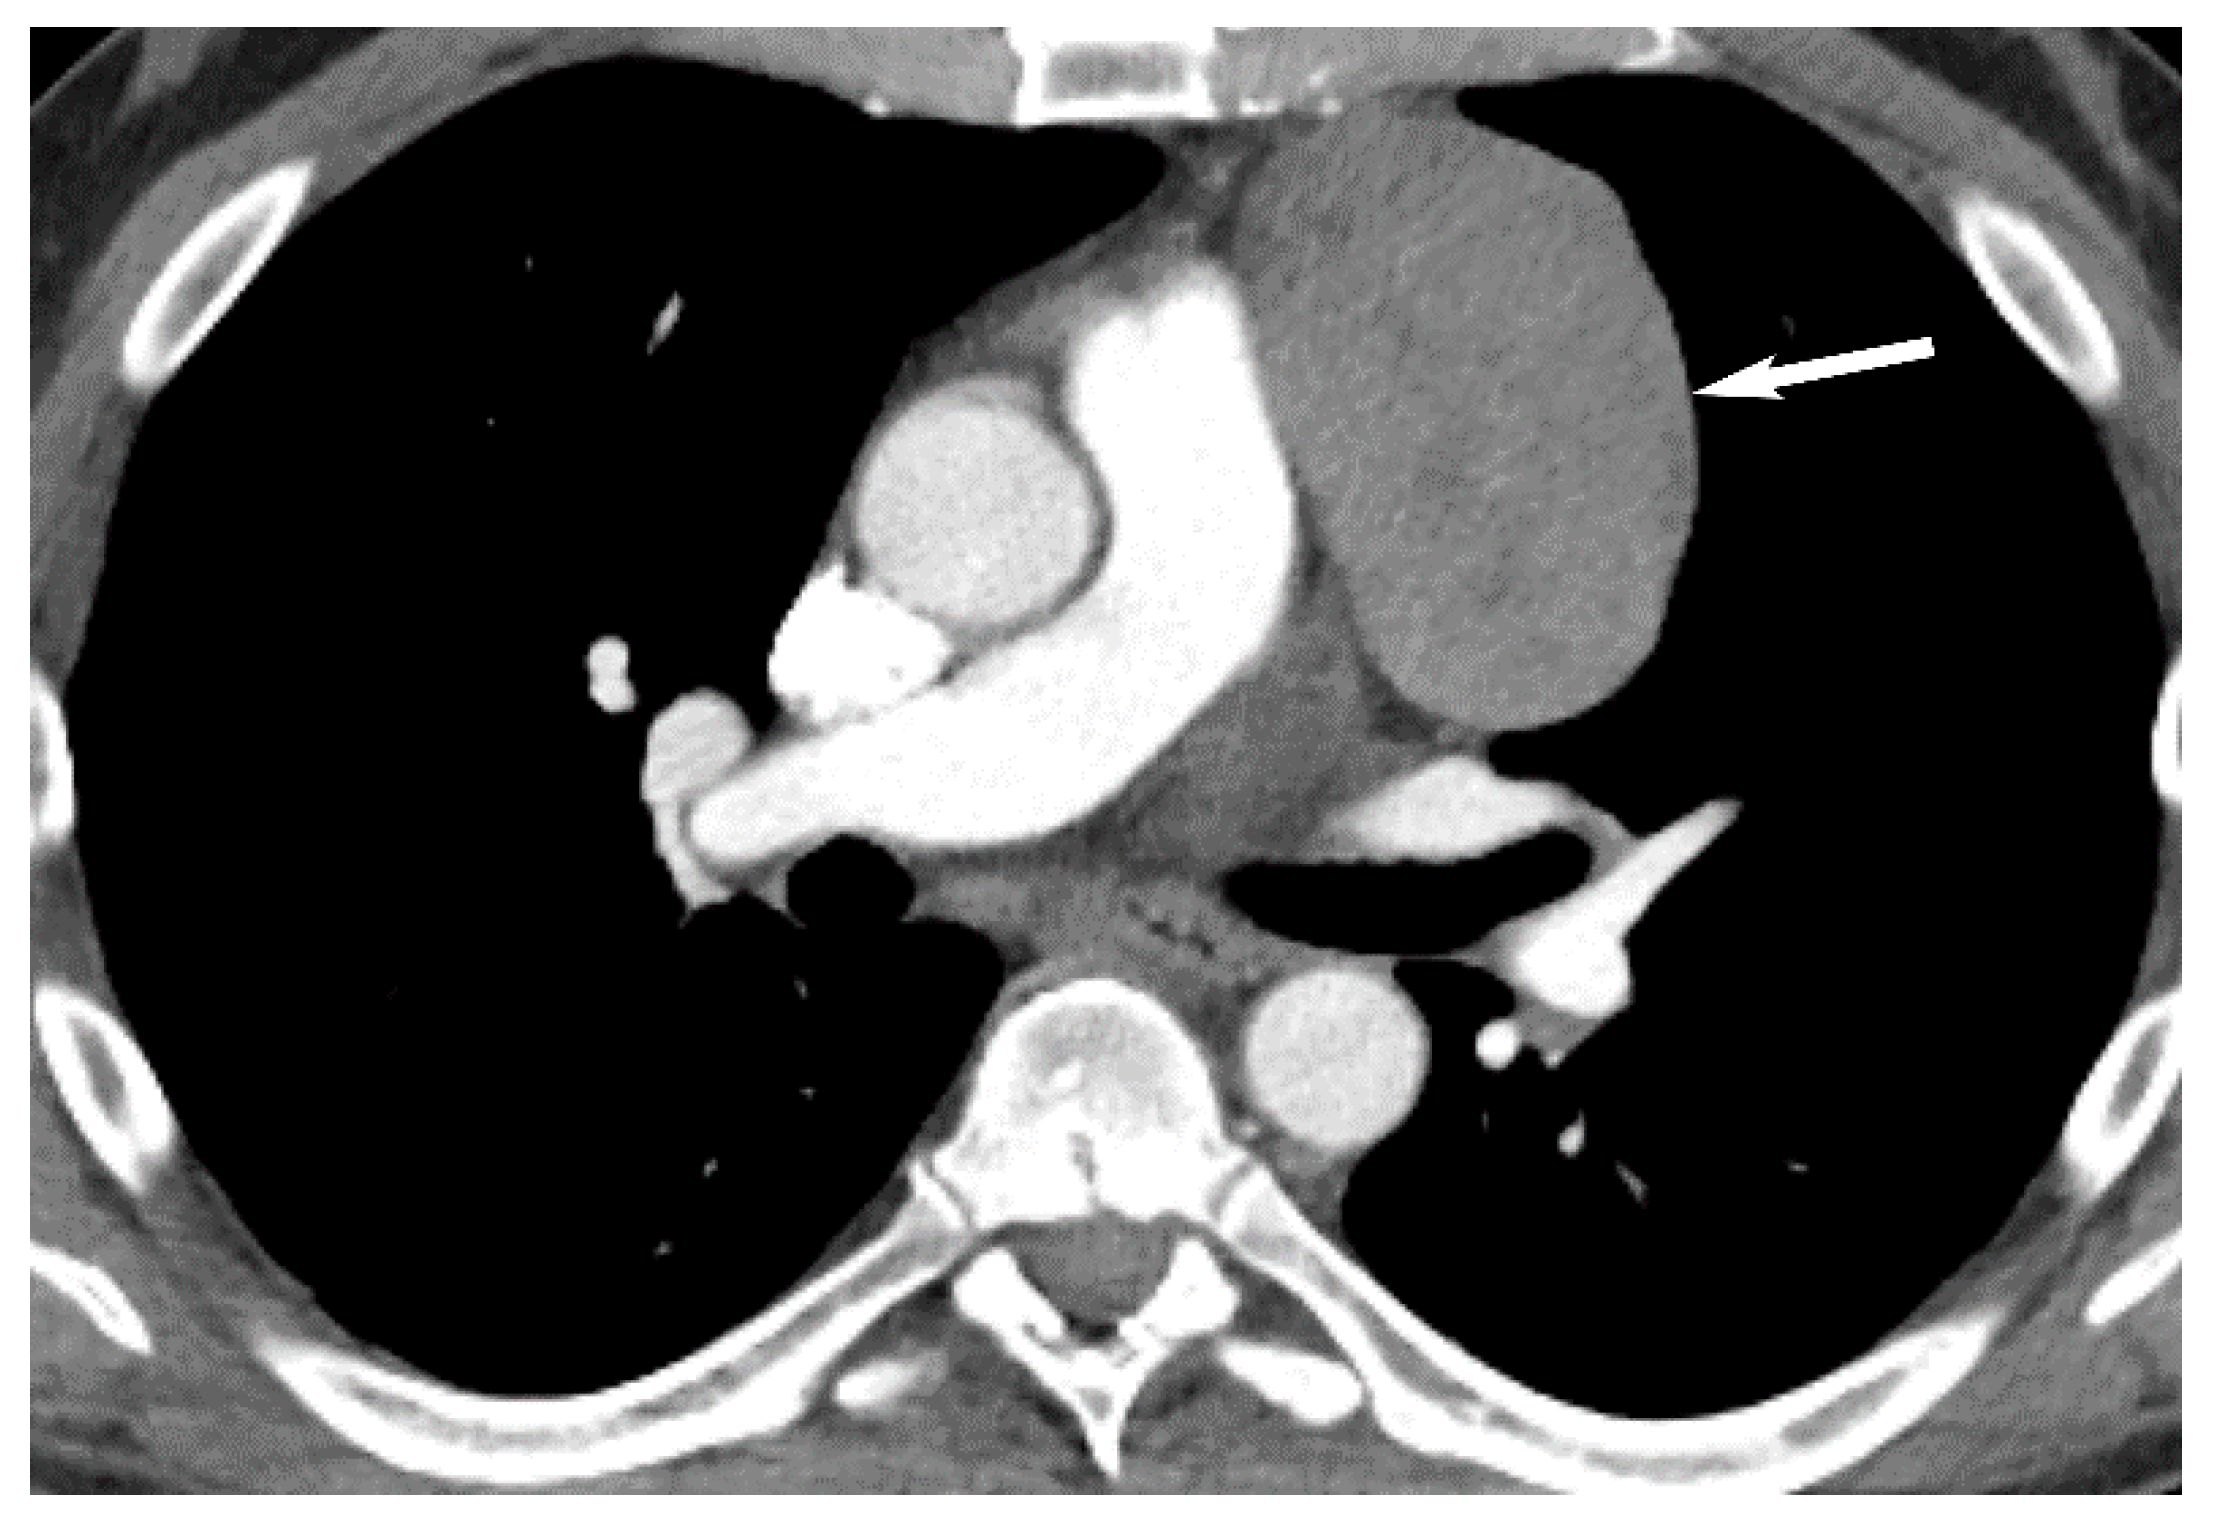

7. Germ Cell Tumors

9. Hypervascular Lesions